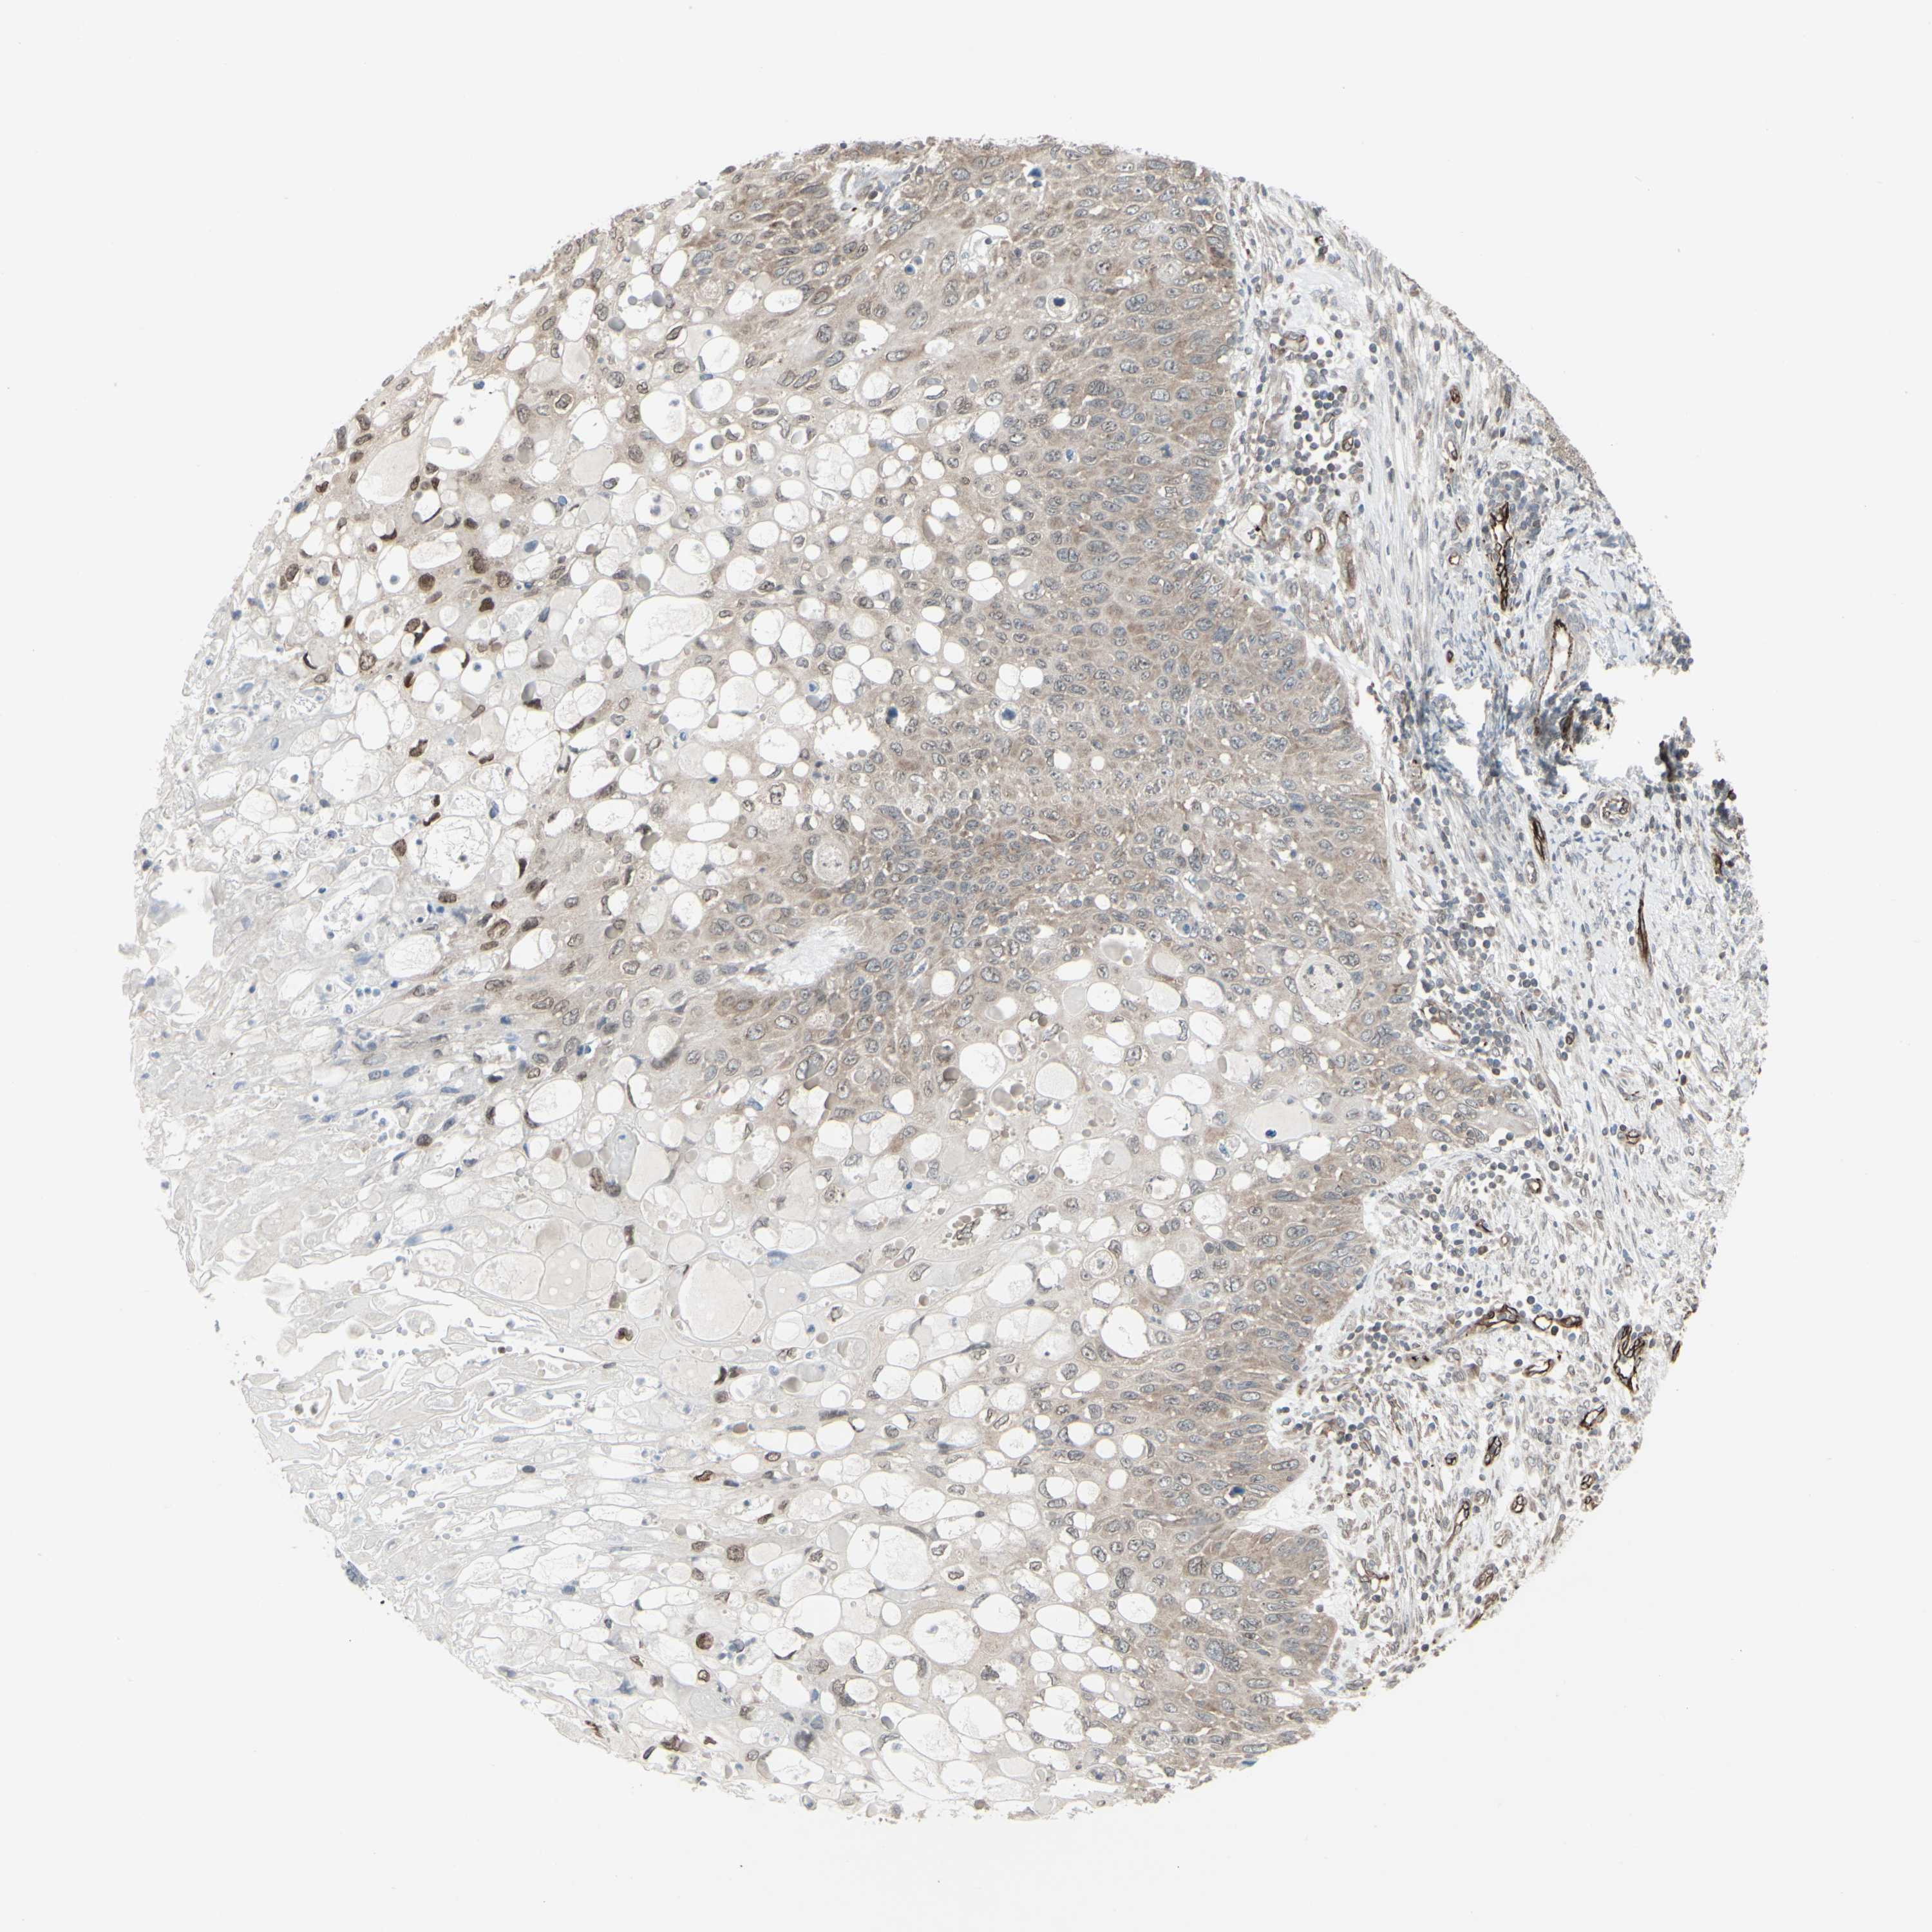

CERVICAL CANCER - Protein expressioni

A mouse-over function shows sample information and annotation data. Click on an image to view it in a full screen mode. Samples can be filtered based on level of antibody staining by selecting one or several of the following categories: high, medium, low and not detected. The assay and annotation is described here.

Note that samples used for immunohistochemistry by the Human Protein Atlas do not correspond to samples in the TCGA dataset.

Antibody stainingi

Antibody staining in the annotated cell types in the current human tissue is reported as not detected, low, medium, or high, based on conventional immunohistochemistry profiling in selected tissues. This score is based on the combination of the staining intensity and fraction of stained cells.

Each image is clickable and will lead to virtual microscopy that enables deeper exploration of all samples and also displays staining intensity scores, fraction scores and subcellular localization as well as patient and tissue information for each sample.

Antibody HPA010570

Staining

High

Medium

Low

Not detected

Intensity

Strong

Moderate

Weak

Negative

Quantity

>75%

75%-25%

<25%

None

Location

Nuclear

Cytoplasmic/membranous

Cytoplasmic/membranous,nuclear

Squamous cell carcinoma, NOS